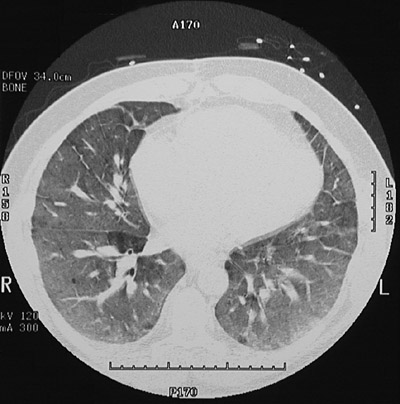

| Note the extensive "ground glass" opacification in the lung fields in this case of idiopathic pulmonary hemosiderosis in this chest CT scan. Note that this appearance could be seen with extensive pulmonary edema and/or hemorrhage as well. Note the septal thickening. |